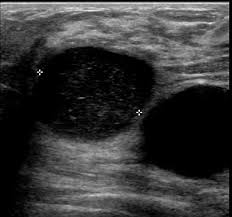

A A Simple Breast Cyst 75 B Breast Ultrasound Showing A Cancer Download Scientific Diagram from www.researchgate.net Instead, breast skin can become thick, red, and look pitted, like an orange peel. Signs of inflammatory breast cancer. Ultrasound images are black and white, showing a small portion of the breast at a time. Below are images of dcis on breast ultrasound. Ibc is a rapidly progressive, aggressive form of breast cancer associated with a low overall survival rate. Looks larger, thicker or heavier. X trustworthy source mayo clinic educational website from one of the world's leading hospitals go to source research suggests that men are more likely to ignore breast lumps than women, but early. Finding breast lumps and seeing change in the size and shape.

Early warning signs of inflammatory breast cancer along with images of inflammatory breast cancer are mentioned below. There is a slight increase in the density in the right breast compared with the left. Rate of dcis discovery is increasing, due to screening mammograms. Cysts, tumors, and growths will appear as dark areas on the scan. Any area that does not look like normal tissue is a possible cause for concern. Finding breast lumps and seeing change in the size and shape. Ultrasound is one of the tools used in breast imaging, but it does not replace annual mammography. When is breast ultrasound used? Ibc is a rapidly progressive, aggressive form of breast cancer associated with a low overall survival rate. Some early breast cancers only show up as calcifications on mammography. Has skin that looks dimpled or ridged like an orange. Generally speaking, the denser the tissue, the whiter it appears. Instead, breast skin can become thick, red, and look pitted, like an orange peel.

Has skin that looks dimpled or ridged like an orange. Density is a term used to describe breast tissue that has many glands close together. You might not need any further tests if everything looks normal. Other ultrasound findings that suggest breast cancer include: Tubular carcinoma of the breast is a subtype of invasive ductal carcinoma (idc). It is the most common cause of cancer death in women. in 2005 alone, 519 000 deaths were recorded due to breast cancer. this means that one in every 100 deaths worldwide and almost one in every 15 cancer deaths were due to breast cancer. Breast ultrasound dataset is categorized into three classes: Ultrasound is one of the tools used in breast imaging, but it does not replace annual mammography. While it may look like a fuzzy, spotty television screen with different shades of grey to a patient, the ultrasound technician and the radiologist use these images to diagnose masses and tumors. The peak age at presentation may be comparatively younger than with other types of breast cancer 7. Signs of inflammatory breast cancer. Cysts, tumors, and growths will appear as dark areas on the scan. You can get dressed straight after the ultrasound.